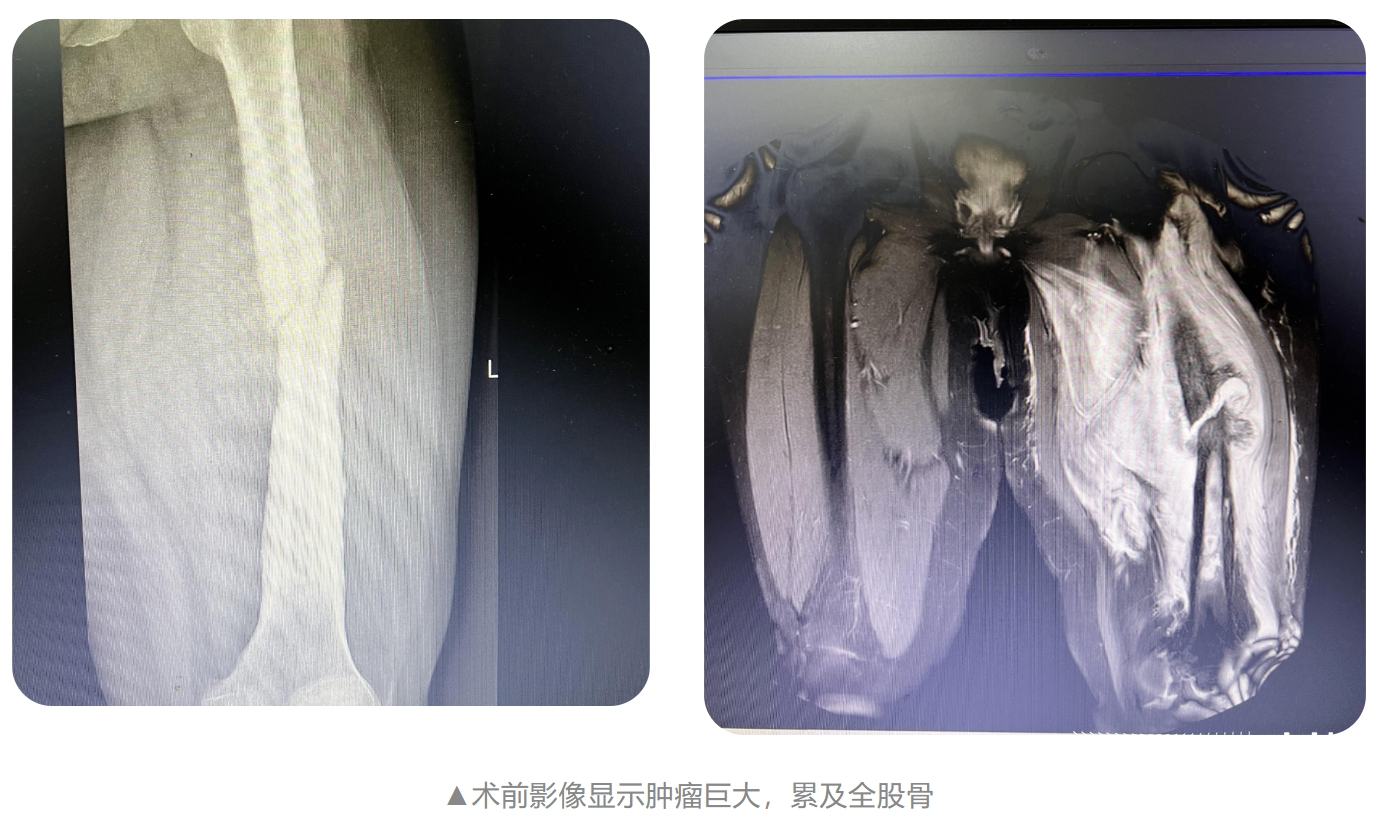

据了解,患者为28岁男性,两年前因直肠癌在其他医院实施了结肠癌根治术,术后经规律化疗、复查,没有出现异常情况。此后,患者在一次偶然地翻身时,出现左侧大腿剧烈疼痛,活动受限一个月后到贵医附院就诊,入院诊断为“左侧股骨巨大恶性肿瘤并病理性骨折”。

贵医附院骨科专家考虑患者还很年轻,且属于单发转移灶,远期生存时间较长,经讨论后决定为他实施“左侧全股骨巨大肿瘤切除+全股骨置换术”。